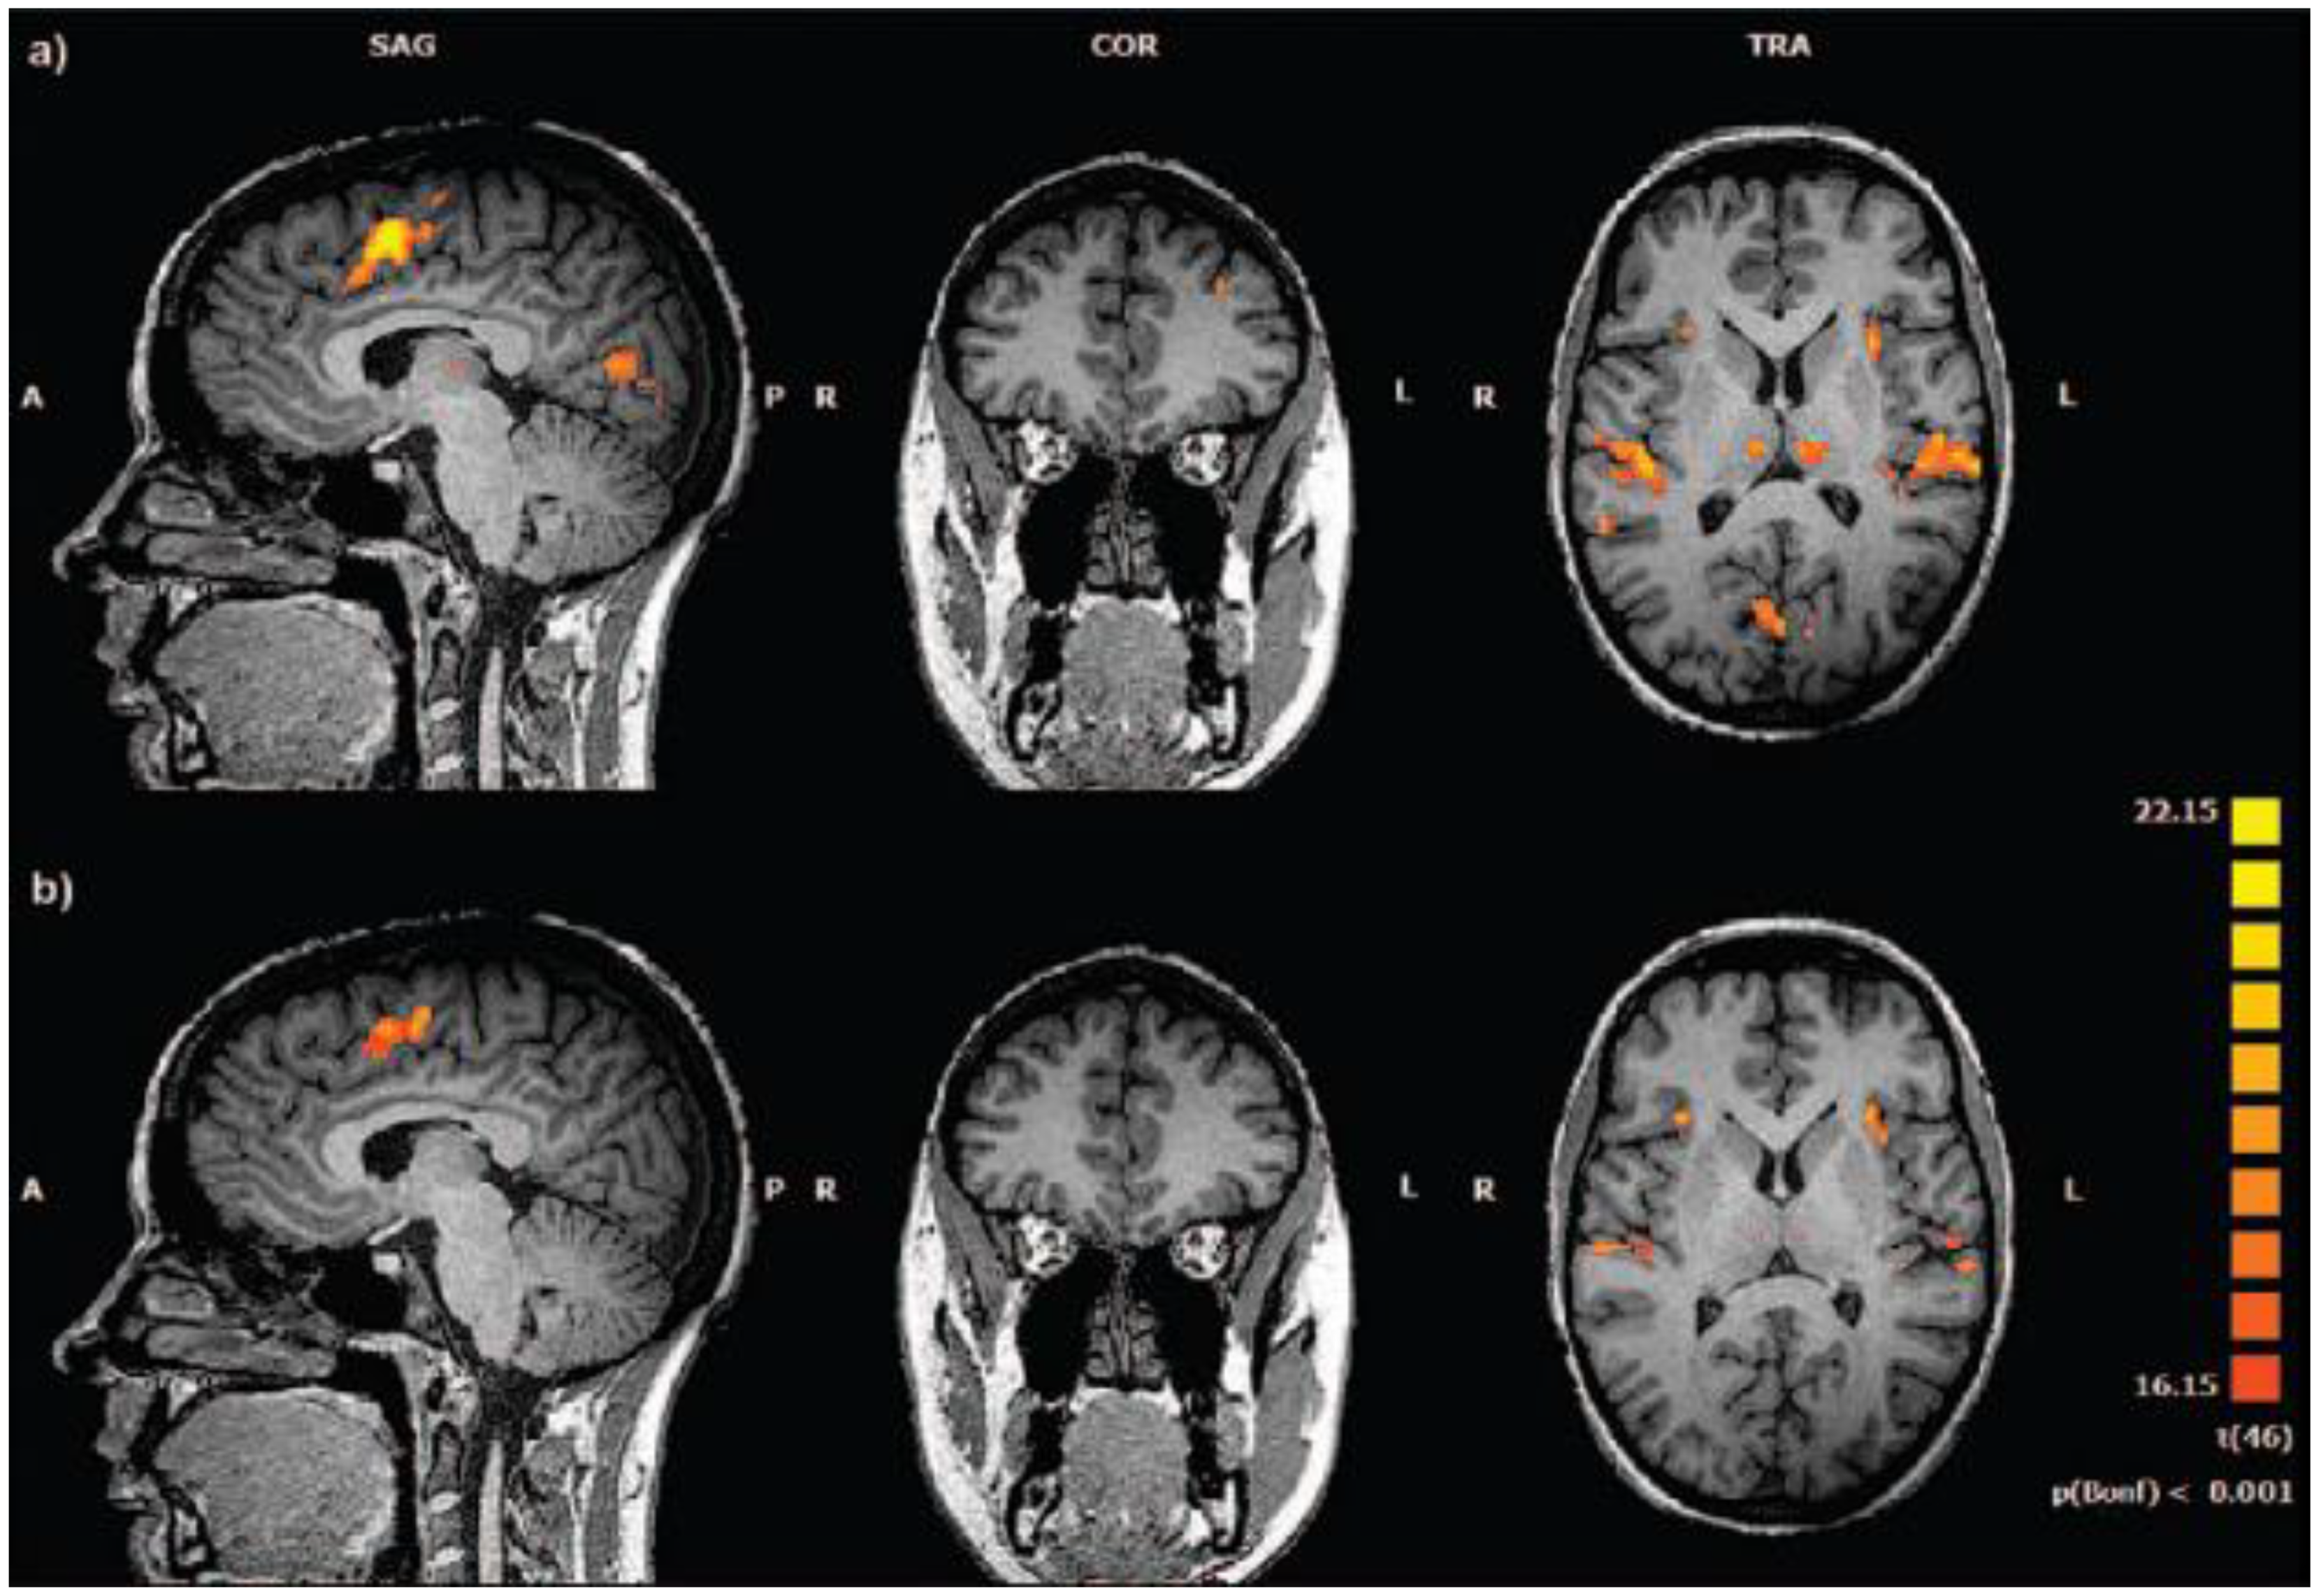

Data Acquisition Approaches and Limitations with a Standalone Setup